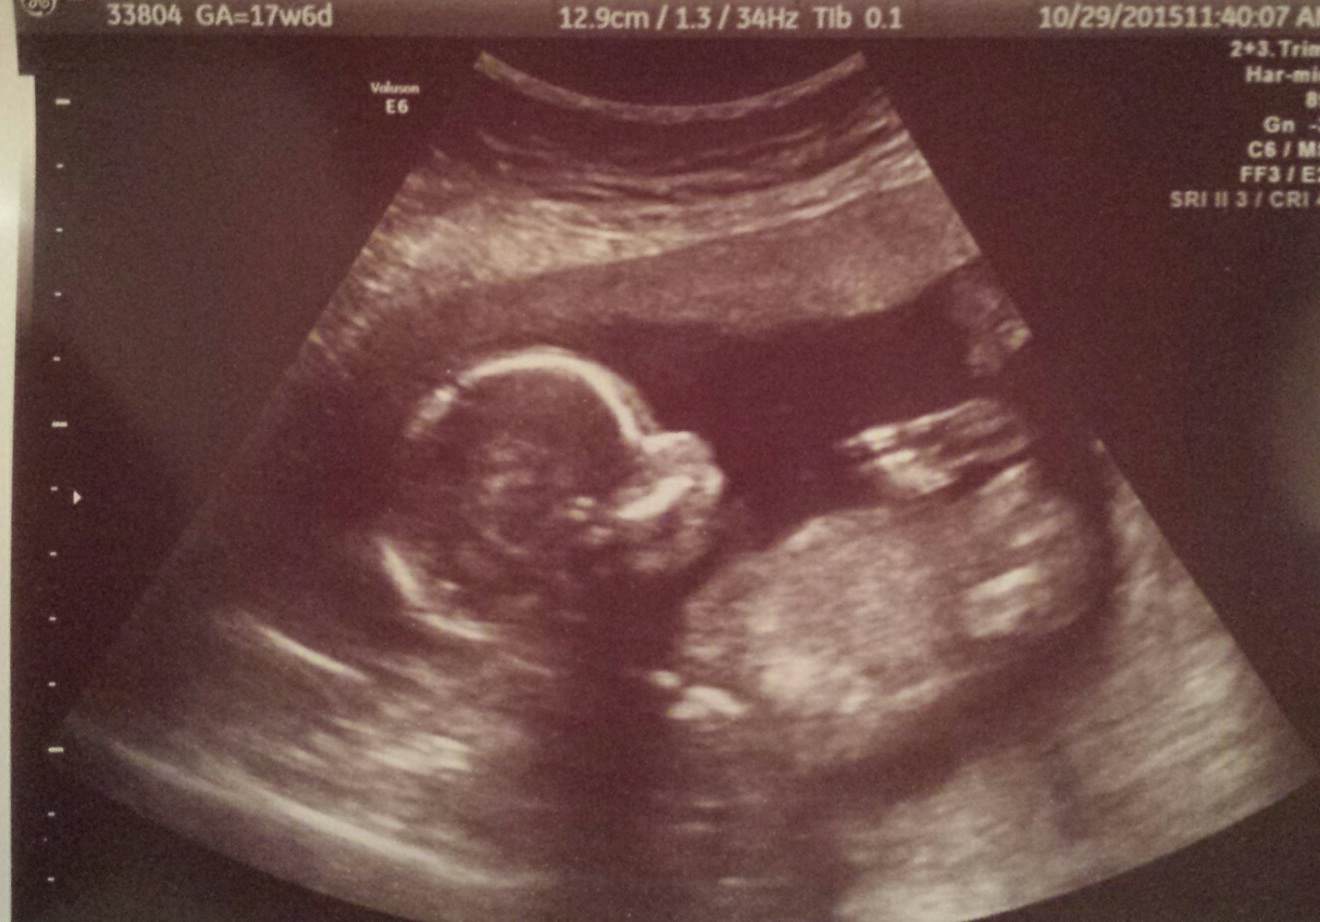

This ultrasound was done at 9w 3d. 12w 1d today . Wish I would have had one done a little further along to see something more . Fhr at 173 bpm. This is baby #2 we're really stoked

12w 1d today . Wish I would have had one done a little further along to see something more . Fhr at 173 bpm. This is baby #2 we're really stoked